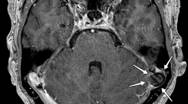

Det lille brok ind i AG kaldes samlet set BHAG, hvilket står for Brain Herniations into Arachnoid Granulations (se billedet). Brokket kan være af forskellig størrelse, men omkring 10 mm er almindeligt. Det kræver således tynde snit og høj opløsning for at kunne se dem. De moderne skannere er netop karakteriseret ved at skanne med tyndere snit og højere opløsning, så man må forvente at se flere af dem fremadrettet.